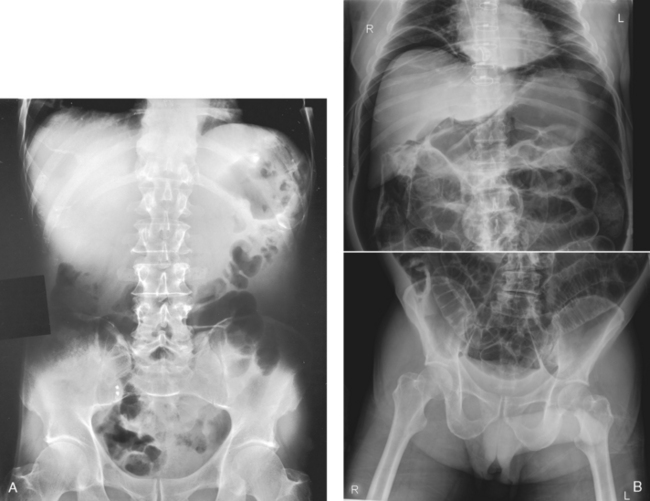

Structures shown: This projection shows the following: the inferior margin of the liver; the spleen, kidneys, and psoas muscles; calcifications; and evidence of tumor masses. If the image includes the upper abdomen and diaphragm, the size and shape of the liver may be seen (Fig. 28-15).

Fig. 28-15 Mobile AP abdomen radiographs. A, Abdomen without pathology. The entire abdomen is seen in this patient. B, Because of this patient’s increased body habitus, two crosswise (landscape) images of the abdomen were necessary to include all abdominal structures. Counting vertebral bodies ensures adequate overlap. Note large amount of free air indicative of a perforated bowel.